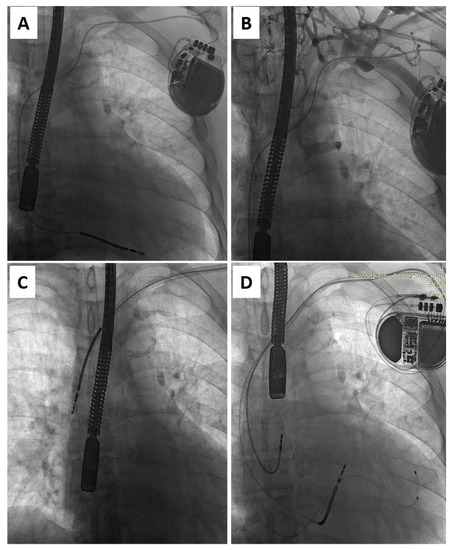

Zero-Fluoroscopy Catheter Ablation of Right Appendage Focal Atrial Tachycardia in a Pregnant Woman

Clin. Pract. 2024, 14(3), 946-953; https://doi.org/10.3390/clinpract14030075 - 21 May 2024

Background: Arrhythmias in pregnancy are complex to manage due to the teratogenic effects of many antiarrhythmic drugs and the common use of ionizing radiation during catheter ablation procedures. Furthermore, pregnant women are extremely vulnerable and difficult to treat because of the progressive physical [...] Read more.

Background: Arrhythmias in pregnancy are complex to manage due to the teratogenic effects of many antiarrhythmic drugs and the common use of ionizing radiation during catheter ablation procedures. Furthermore, pregnant women are extremely vulnerable and difficult to treat because of the progressive physical and hormonal changes that occur during the nine months of pregnancy. Case Presentation: In this case report, we describe a complex clinical case of a 34-year-old pregnant woman who was affected by an incessant right atrial tachycardia, with signs and symptoms of initial hemodynamic instability. This tachycardia was refractory to antiarrhythmic drugs, so a zero-fluoroscopy ablation was performed. The first procedure was complicated by cardiac tamponade, quickly resolved without further complications for the mother or the fetus. In the following days, a deep venous thrombosis occurred at the femoral venous access. After a few days, the patient underwent a second procedure that was successful and resulted in the restoration of a sinus rhythm. Conclusions: The management of this clinical case was complex both from a procedural and a clinical (cardiological and gynecological) point of view. Finally, the integration of the various skills led to an excellent result. Full article